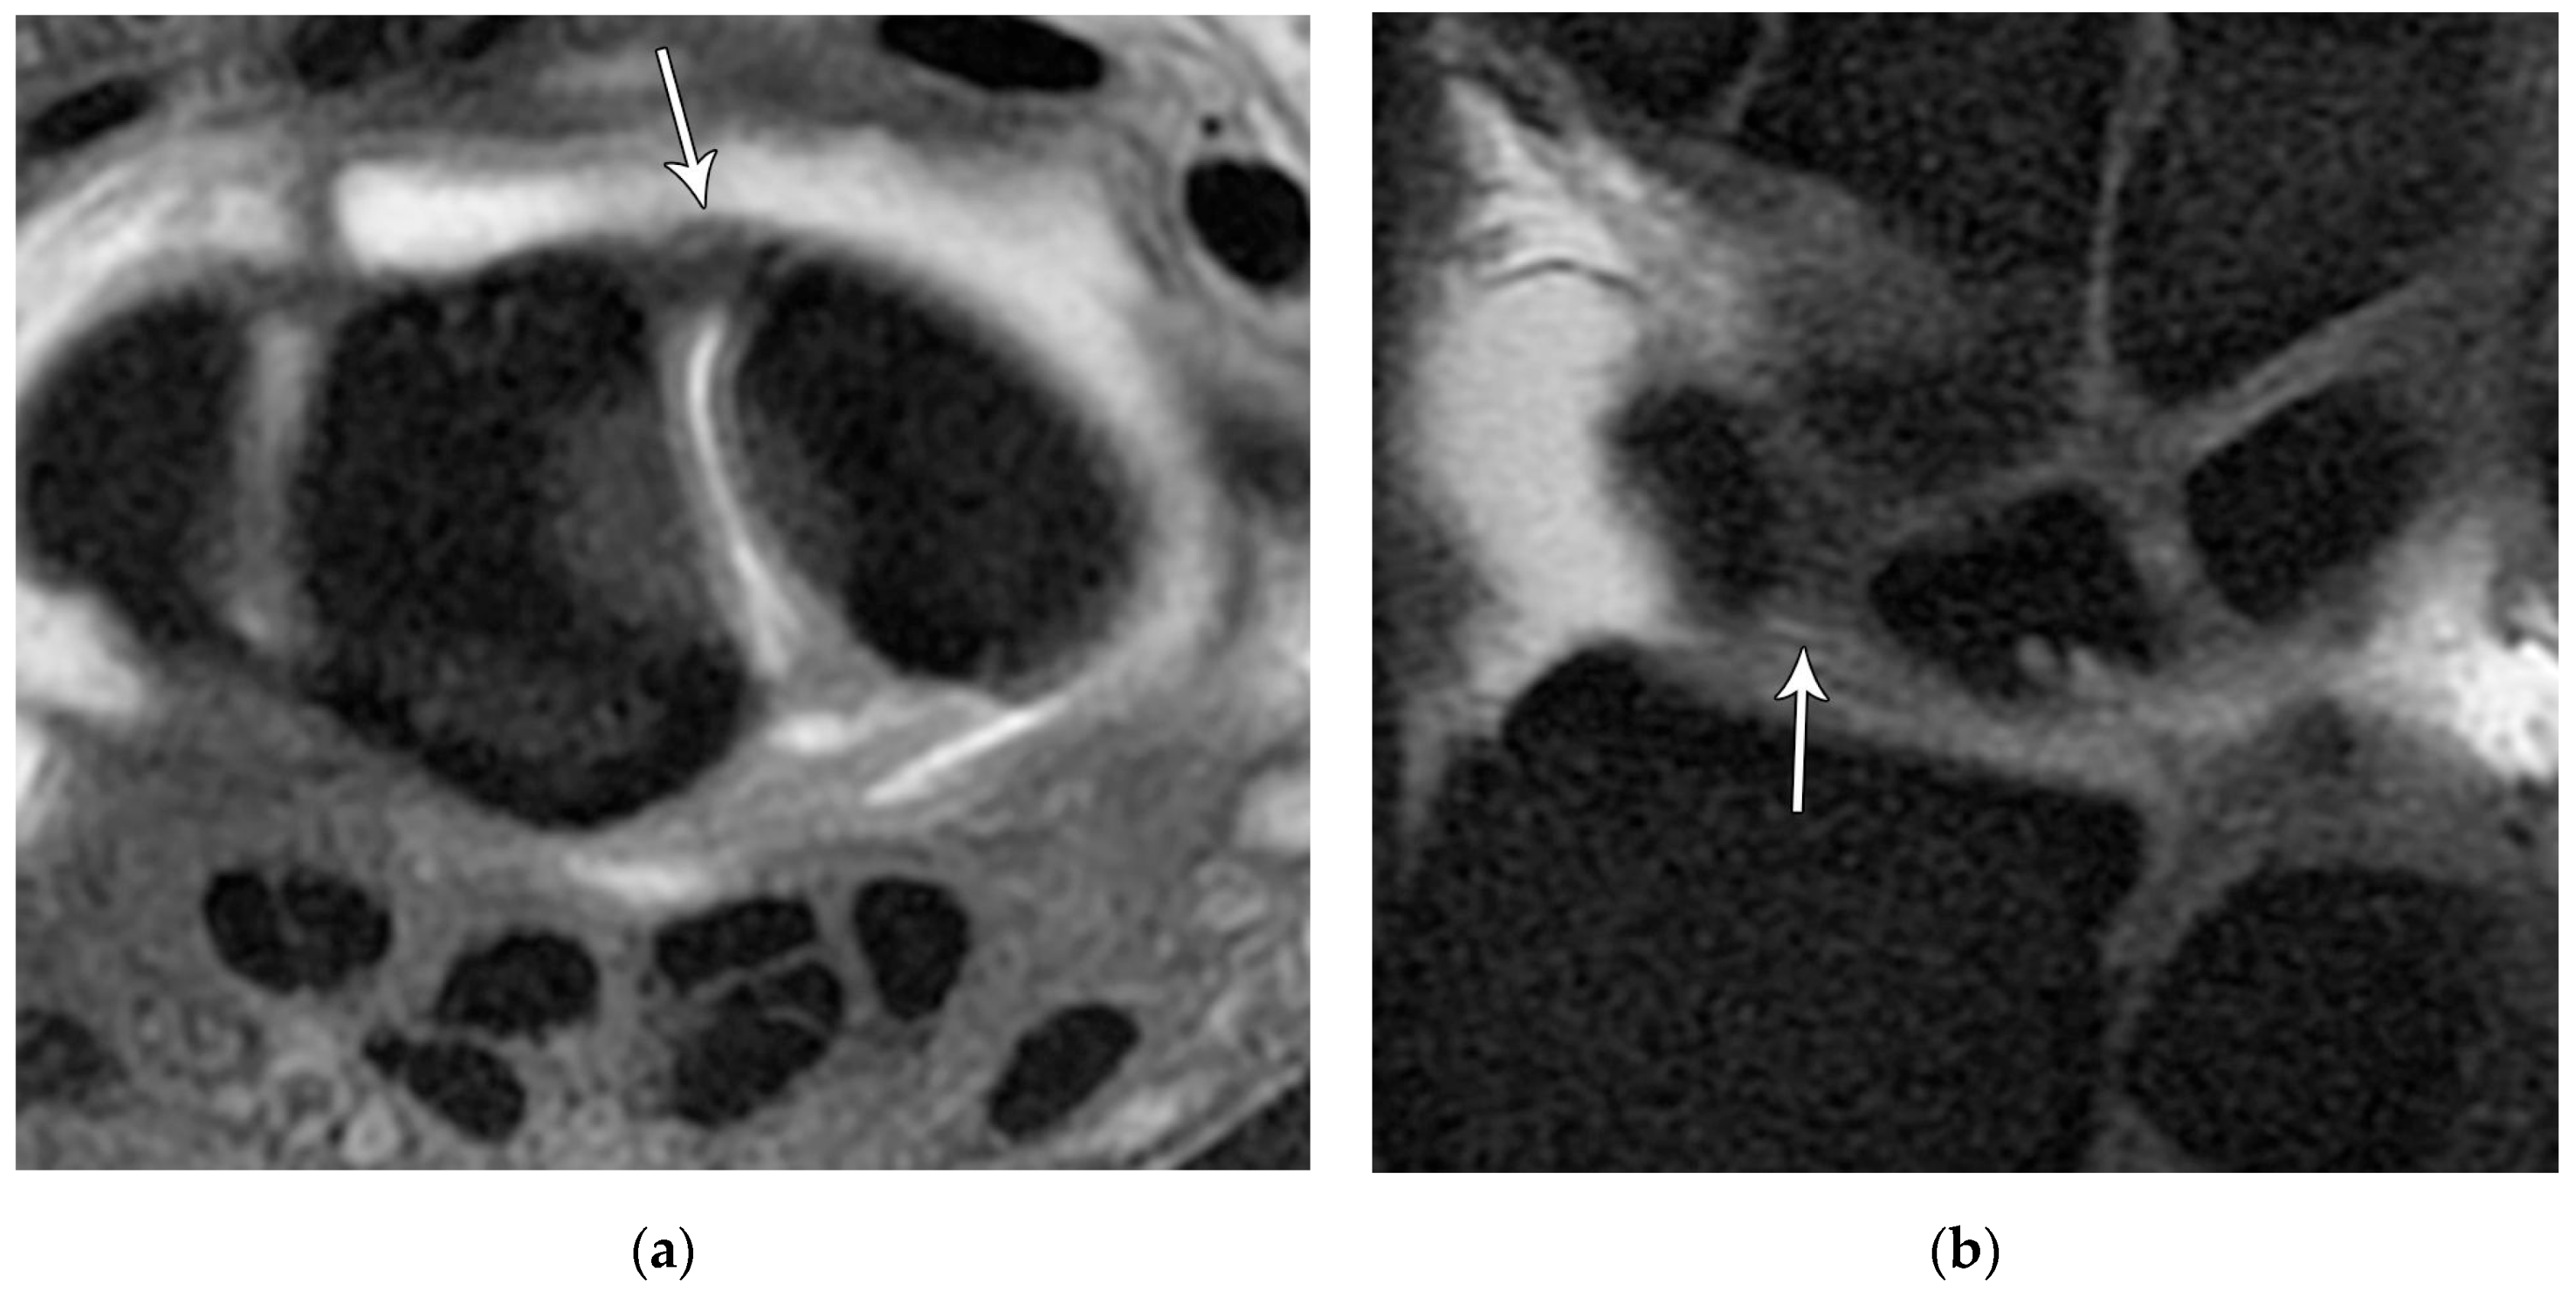

Figure 22. (a) Axial T1 FS MR arthrogram images showing a normal thick dorsal scapholunate ligament (arrow). (b) In a different patient, coronal T1 FS MR arthrogram images showing a normal thick dorsal scapholunate ligament (arrow).

The scapholunate ligament can be thought of as having three separate components: proximal, dorsal, and volar (Figure 20) [2,14]. Tears are often traumatic in etiology (e.g., fall on outstretched hand or FOOSH) and associated with symptoms. The proximal component is also known as the “central membranous component” due to its location and composition (Figure 21a). Partial tears or degenerative perforations of this membranous portion are common and usually asymptomatic. Typically, this portion has a triangular, meniscal projection distally (Figure 21b,c). The dorsal component is the thickest and has the most significant role functionally (Figure 22). The volar component is thin and weak and, therefore, is not of great biomechanical importance, and isolated injury is uncommon.